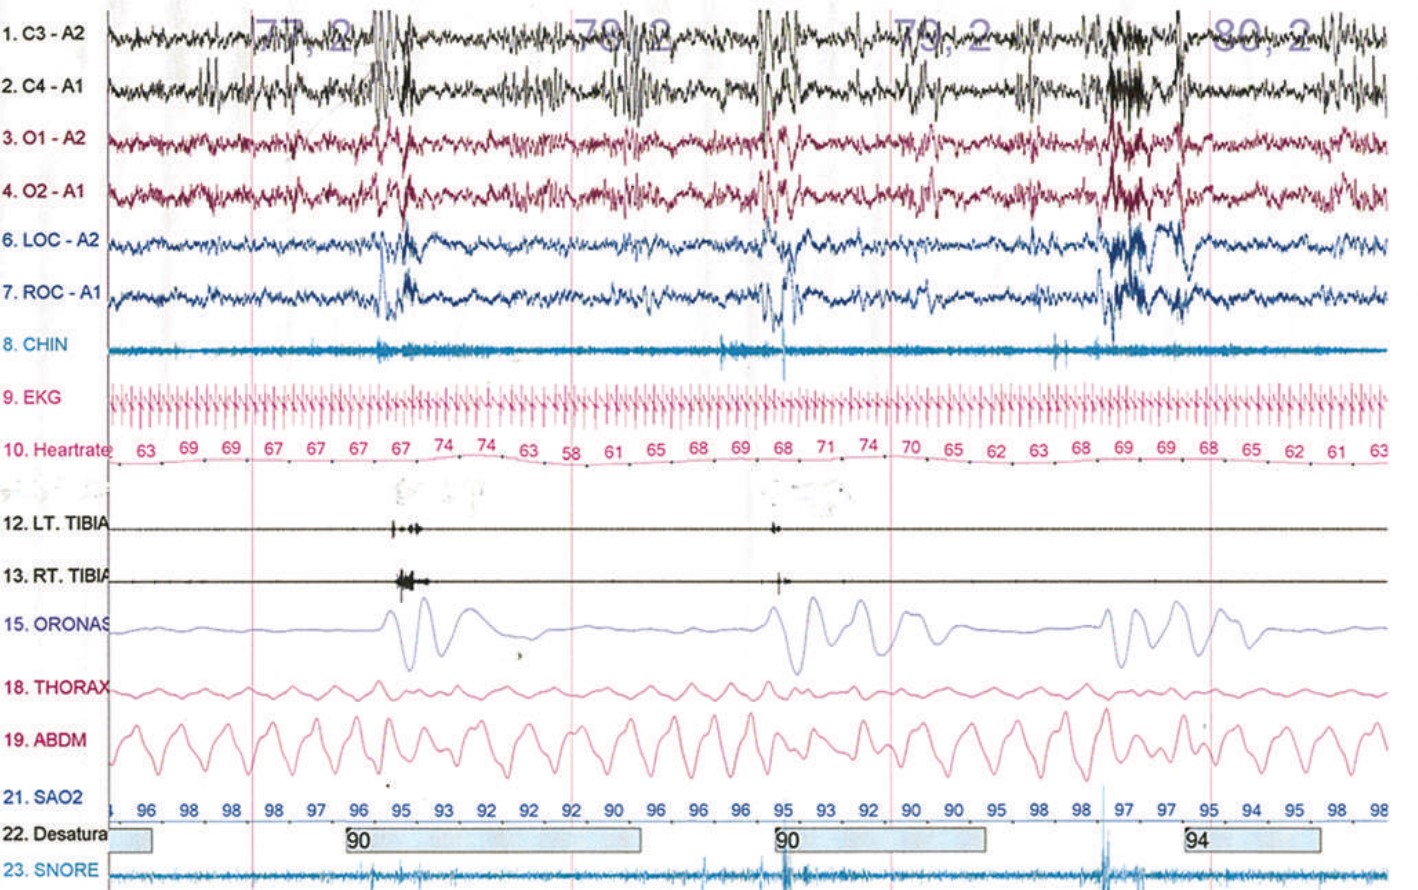

Question: The figure below shows a 120-second segment from an overnight polysomnogram. Which of the following is demonstrated in the picture?

Correct Answer: Obstructive apnea

Explaination: This demonstrates obstructive sleep apnea. In the oronasal channel, flow of air stops four different times (indicated by the flat line). During this same time the thorax and abdominal channels have continued effort. A central apnea occurs when there is no airflow and nothoracic or abdominal effort. A mixed apnea starts initially with no flow and no effort, but near the end effort begins without any airflow. Cheyne-Stokes breathing involves bursts of progressively faster and deeper breaths with a gradual decrease and stop of respiration. This is a type of central apnea. Paradoxical breathing occurs when airflow is positive with positive thoracic effort and negative abdominal effort. This implies inspiration is caused by thoracic muscles rather than diaphragmatic excursion